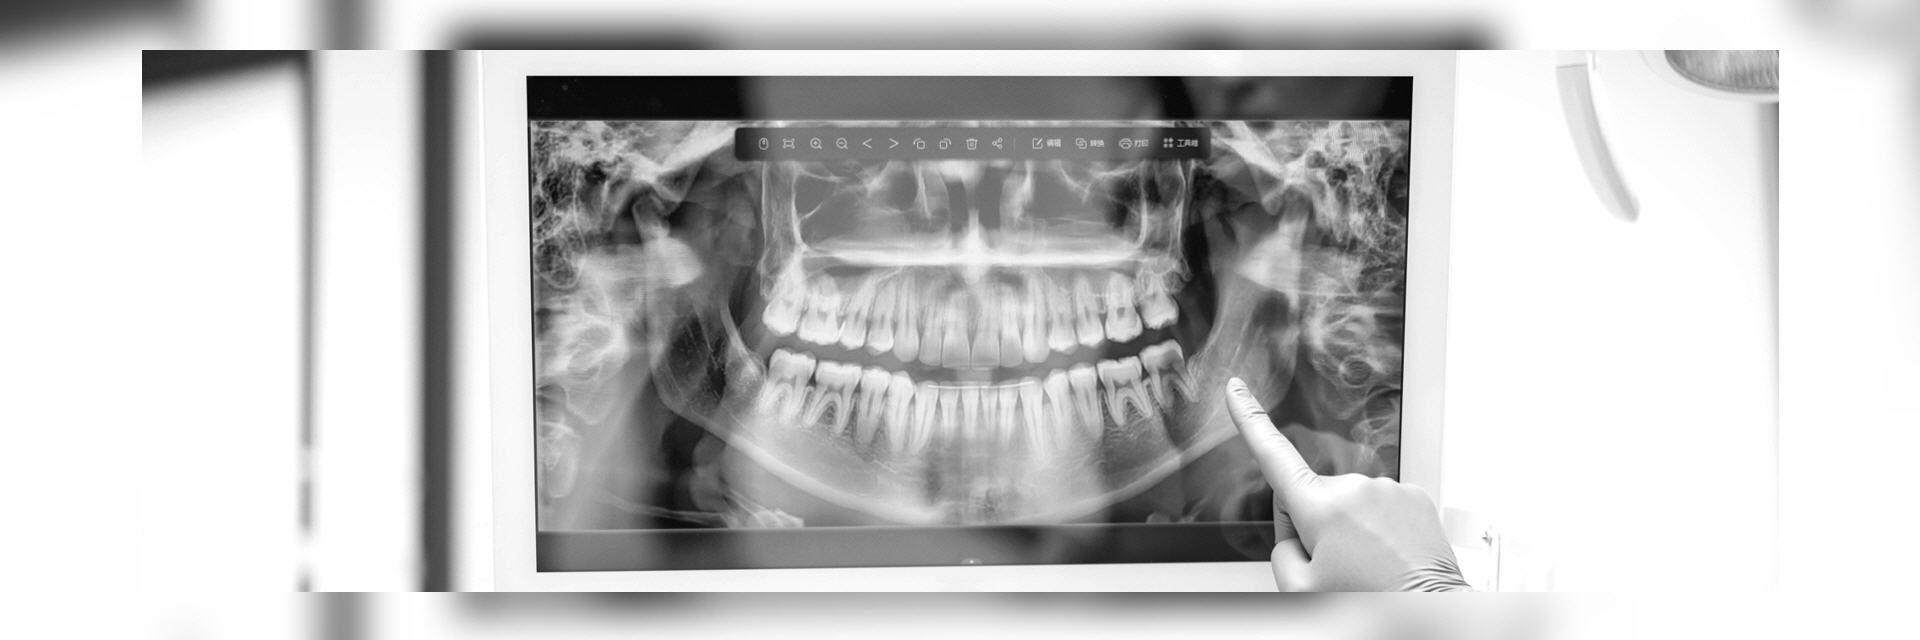

- Orthopantomogramm (OPG) ist eine Panoramaschichtaufnahme des gesamten Ober- und Unterkiefers inkl. der Kiefergelenke in 2-dimensionaler Darstellung. Das Verfahren ist schmerzfrei, strahlenarm und auch bei Würgereiz problemlos durchführbar. Dieses Bild gibt dem Zahnarzt eine Gesamtübersicht und ermöglicht eine Beurteilung der Zahnzwischenräume, der im Knochen befindlichen Wurzeln,

Im digitalen Röntgenbild sehen wir die Vorgeschichte Ihrer Zähne. Also die Spuren des Lebens, die dieses an den Zähnen hinterlassen hat. Dies betrifft Erkrankungen wie die Karies, Spalten unter Kronen oder Füllungen, Wurzelbehandlungen, Entzündungen im Knochen, aber auch Beläge und deren Auswirkungen auf den Zahnhalteapparat also den umgebenden Knochen.

Somit ergeben sich anhand des Ist-Zustands auch Rückschlüsse auf die in Zukunft zu erwartenden Probleme, die selbst im Anfangsstadium noch nicht wahrgenommen werden, sondern erst wenn zum Beispiel die Zerstörung des Zahnhalteapparats durch die Parodontitis bereits weit fortgeschritten ist.